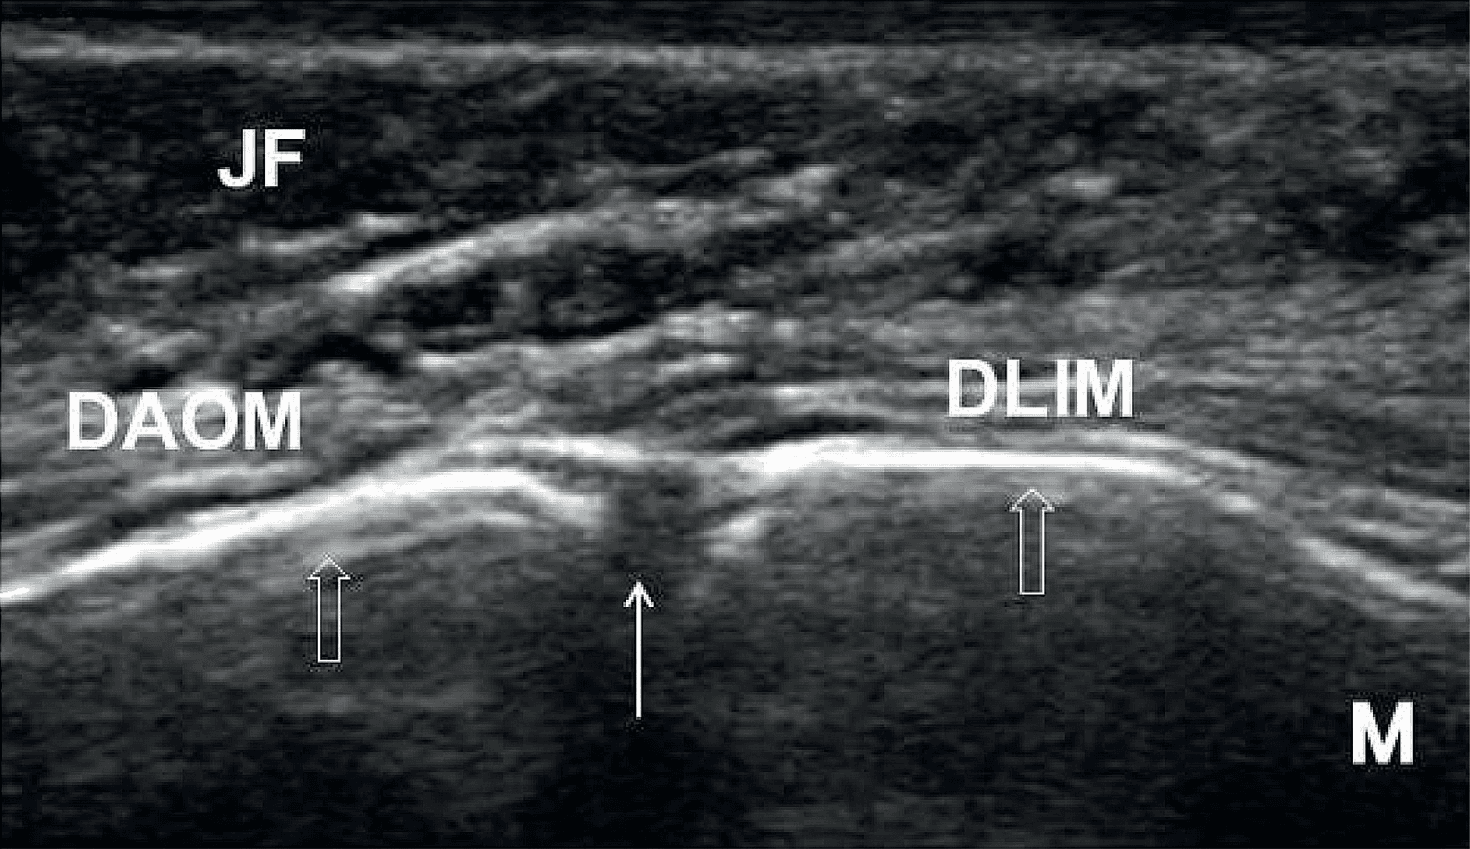

상완신경총 - Figure 7 - 원문 캡션입니다 (자동 번역 실패 — 원문 표기): Figure 7.  Doppler ultrasound imaging of Figure 7. 원문 캡션입니다 (자동 번역 실패 — 원문 표기): Figure 7. Doppler ultrasound imaging of the transverse cervical artery, thyrocervical trunk ( A ), suprascapular artery and nerve ( B ), vertebral artery ( C ), and radicular artery ( D ). AP: articular pillar; AS: anterior scalene muscle; CCA: common carotid artery; IT: inferior trunk; LOC: longus colli muscle; LS: levator scapulae muscle; MT: middle trunk; OMH: omohyoid muscle; SCA: subclavian artery; SCM: sternocleidomastoid muscle; ST: superior trunk; SUA: suprascapular artery; TCA: transverse cervical artery; VA: vertebral artery. Yellow arrowhead: suprascapular nerve; Red arrowhead: radicular artery. The yellow dashed area encircles the brachial plexus, and the blue rectangles in the bottom-right corners represent the transducer position.